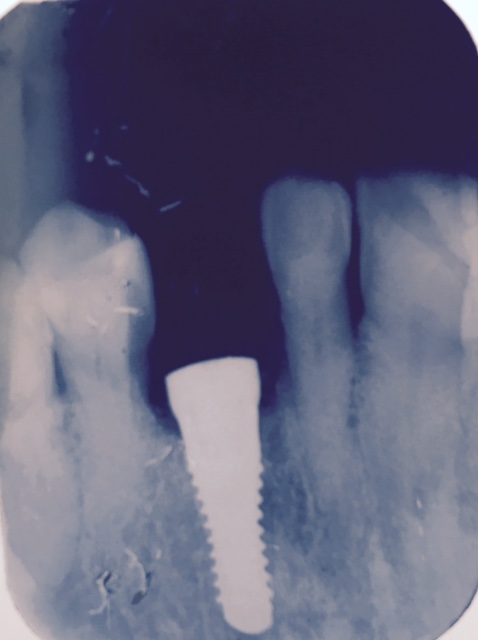

InseriImpianto post estrattivo con RIGENERAZIONE OSSEA E MEMBRANA CON L'USO DI PIEZO PER FRATTURA 23

Paziente di 80 anni. Presenta dolore e ascesso gengivale in sede 23 per frattura coronale e radicolare. Si instaura terapia antibiotica Augmentin 1 gr. 2 volte al di'. Dopo 3 giorni in sedazione cosciente si estrae radice con piezo e dopo accurato curettage osseo si inserisce impianto STRAUMANN Roxolid TE 10 mm. Nel difetto osseo vestibolare viene inserito BIO-OSS e MEMBRANA riassorbibile. Sutura estroflettente Rocefin 1 gr. im per 6 giorni

Pz di 80 anni. presenta dolore e ascesso gengivale in sede 23 per frattura coronale e radicolare si instaura terapia antibiotica Augmentin 1 gr. 2 volte al di'.Dopo 3 giorni in sedazione cosciente si estra e radice con piezo , e dopo accurato curettage osseo si inserisce impianto STRAUMANN Roxolid TE 10 mm. ,nel difetto osseo vestibolare viene inserito BIO-OSS e MEMBRANA riassorbibile. Sutura estroflettente .Rocefin 1 gr. im per 6 giorni

INNESTO IMPIANTO STAUMANN TE ROXOLID e BIOSS